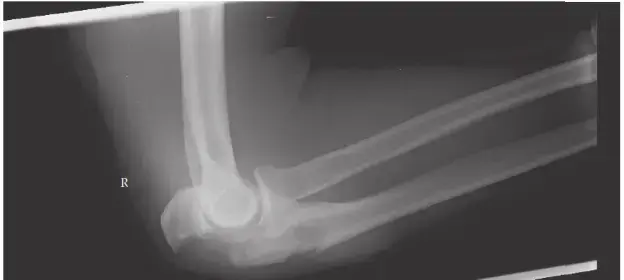

الأشعة السينية (X-rays):

- تُؤخذ صور متعددة (أمامية خلفية AP، جانبية Lateral، ومائلة Oblique) للركبة.

- تُظهر الأشعة السينية وجود الكسر، وموقعه، ونمطه الأولي (على سبيل المثال، إذا كان هناك كسر إسفيني أو انضغاطي).

- تساعد في تصنيف الكسر وفقًا لتصنيف Schatzker.

- يتمتع الأستاذ الدكتور محمد هطيف بخبرة استثنائية في قراءة وتفسير أدق التفاصيل في صور الأشعة السينية، مما يمكّنه من تقدير شدة الكسر ومدى تضرر السطح المفصلي.